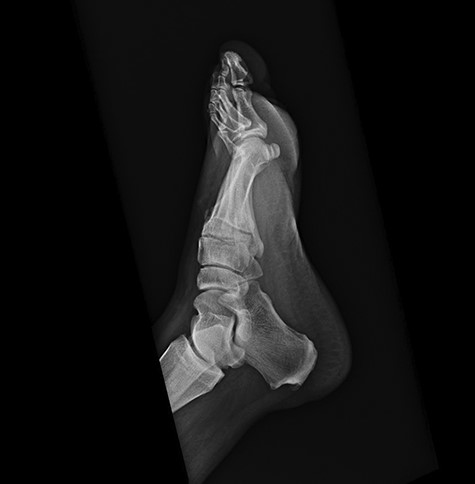

On physical examination, the only significant findings included morbid obesity and a ‘small red tender lesion’ resembling an ‘abscess or fluid collection at the bottom of his foot’ (Fig. 1). X-ray of the patient’s foot was interpreted as ‘soft tissue swelling’ (Fig. 2). The patient was treated with antibiotics for the initial impression of cellulitis and sepsis.

Initial x-ray of the foot was interpreted as ‘soft tissue swelling of the foot’.